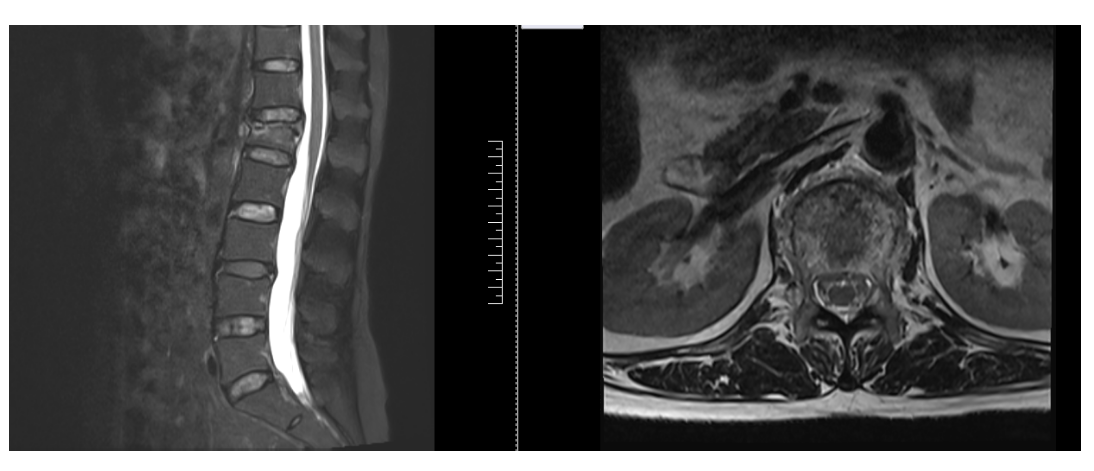

主诉:腰部疼痛3小时

现病史:患者3小时前不慎摔倒后出现腰部疼痛,活动时明显,休息时轻微缓解。不伴下肢麻木等,至当地医院诊治,查腰椎正侧位X线:L1椎体压缩性改变,考虑骨折。今日为求诊治,来我院椎间盘科,以“骨质疏松症,L1椎体骨质疏松性压缩骨折,冠心病”为诊断收住我科。发病以来,饮食正常,睡眠一般,体力正常,大小便正常。